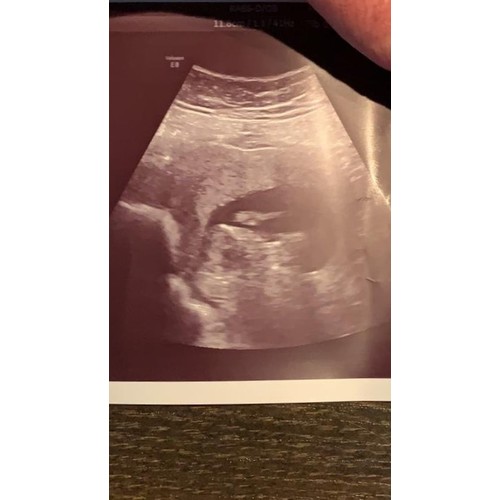

12 weekjes

Ik neig naar jongetje. Had je nog een tweede foto toevallig?

We krijgen een meisje💗

Oh dan was toch de navelstreng boosdoener🙈 Zo zie je maar waarom een tweede foto zo handig kan zijn, je ziet vaak meer.